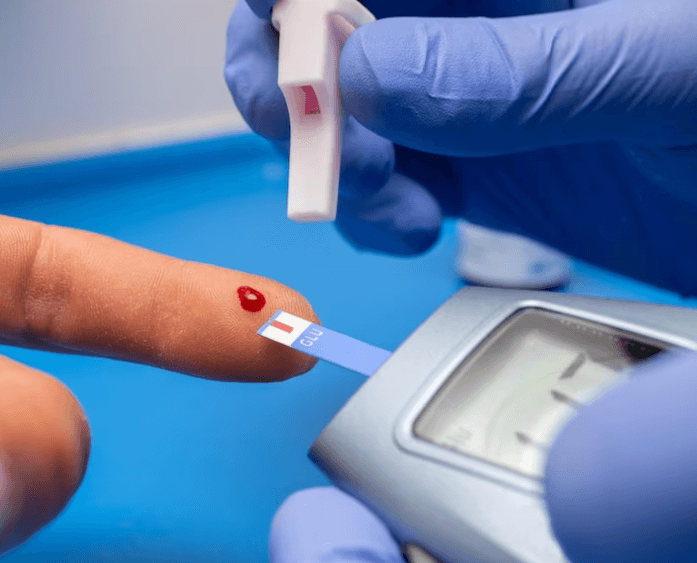

Jak poznat cukrovku: Příznaky, diagnóza a prevence Cukrovka, známá také jako diabetes, je chronické...